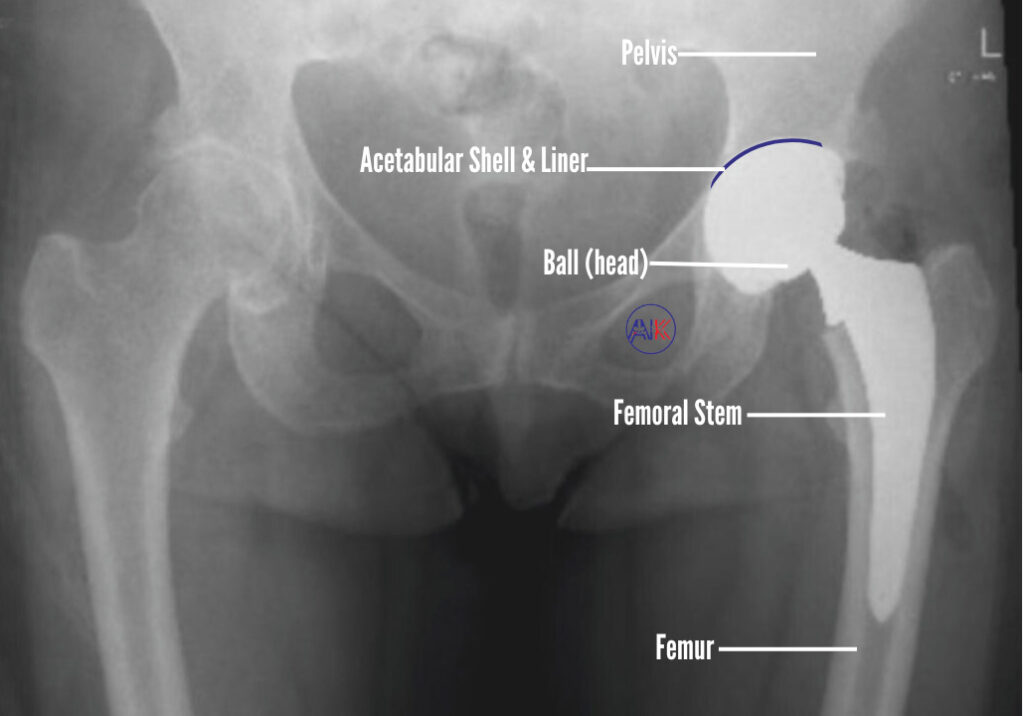

When it comes to hip replacement surgery, the choice of prosthetic implants is crucial for restoring your hip function and relieving pain. These implants are carefully designed systems made up of several components, including the acetabular component (which replaces the hip socket), the femoral component (which replaces the upper part of your thigh bone), and the articular interface (the surface where these components meet). Each part plays an essential role in ensuring the success of your surgery.

The next step involves replacing the removed bone and cartilage with the prosthetic components. The acetabular component (a metal or plastic cup) is placed in the socket, and the femoral component (a metal stem with a ball on top) is inserted into the thigh bone. These components are designed to replicate the natural movement of your hip joint.